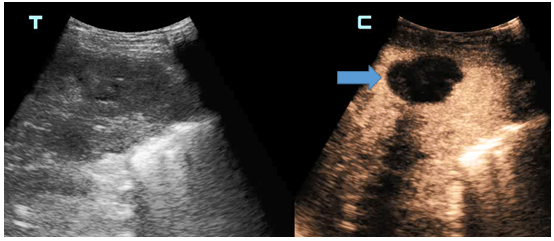

石洪柱介绍,超声造影可在常规超声检查的基础上,通过静脉注射超声造影剂,来增强人体的血流散射信号,实时动态地观察组织的微血管灌注信息,以提高病变的检出率,并对病变的良恶性进行鉴别,是一项新型无创的医学影像学技术,被誉为超声发展史上的“第三次革命”。

德州市第二人民医院超声医学科采用的是目前国际上最先进的肝脏超声造影剂——注射用全氟丁烷微球,进行肝脏超声造影检查和引导下穿刺。注射用全氟丁烷微球是针对肝内巨噬细胞特点及肝肿瘤的血液供应特点研制的造影剂,在肝脏肿瘤诊断与鉴别诊断方面有独特的效果,被业界称为“独特肝脏超声造影”。

在常规超声造影临床应用的基础上,德州市第二人民医院在全市率先将“独特肝脏超声造影技术”应用于临床,不仅标志着该院超声造影再上新台阶,也标志着介入超声技术达到了国内先进水平。目前,德州市第二人民医院利用此种先进造影剂已熟练开展肝脏超声造影,将进一步推动此项技术的临床应用,在肿瘤诊断、介入引导、肿瘤治疗效果评价等方面,为更多患者提供更加精准的诊断与治疗依据。